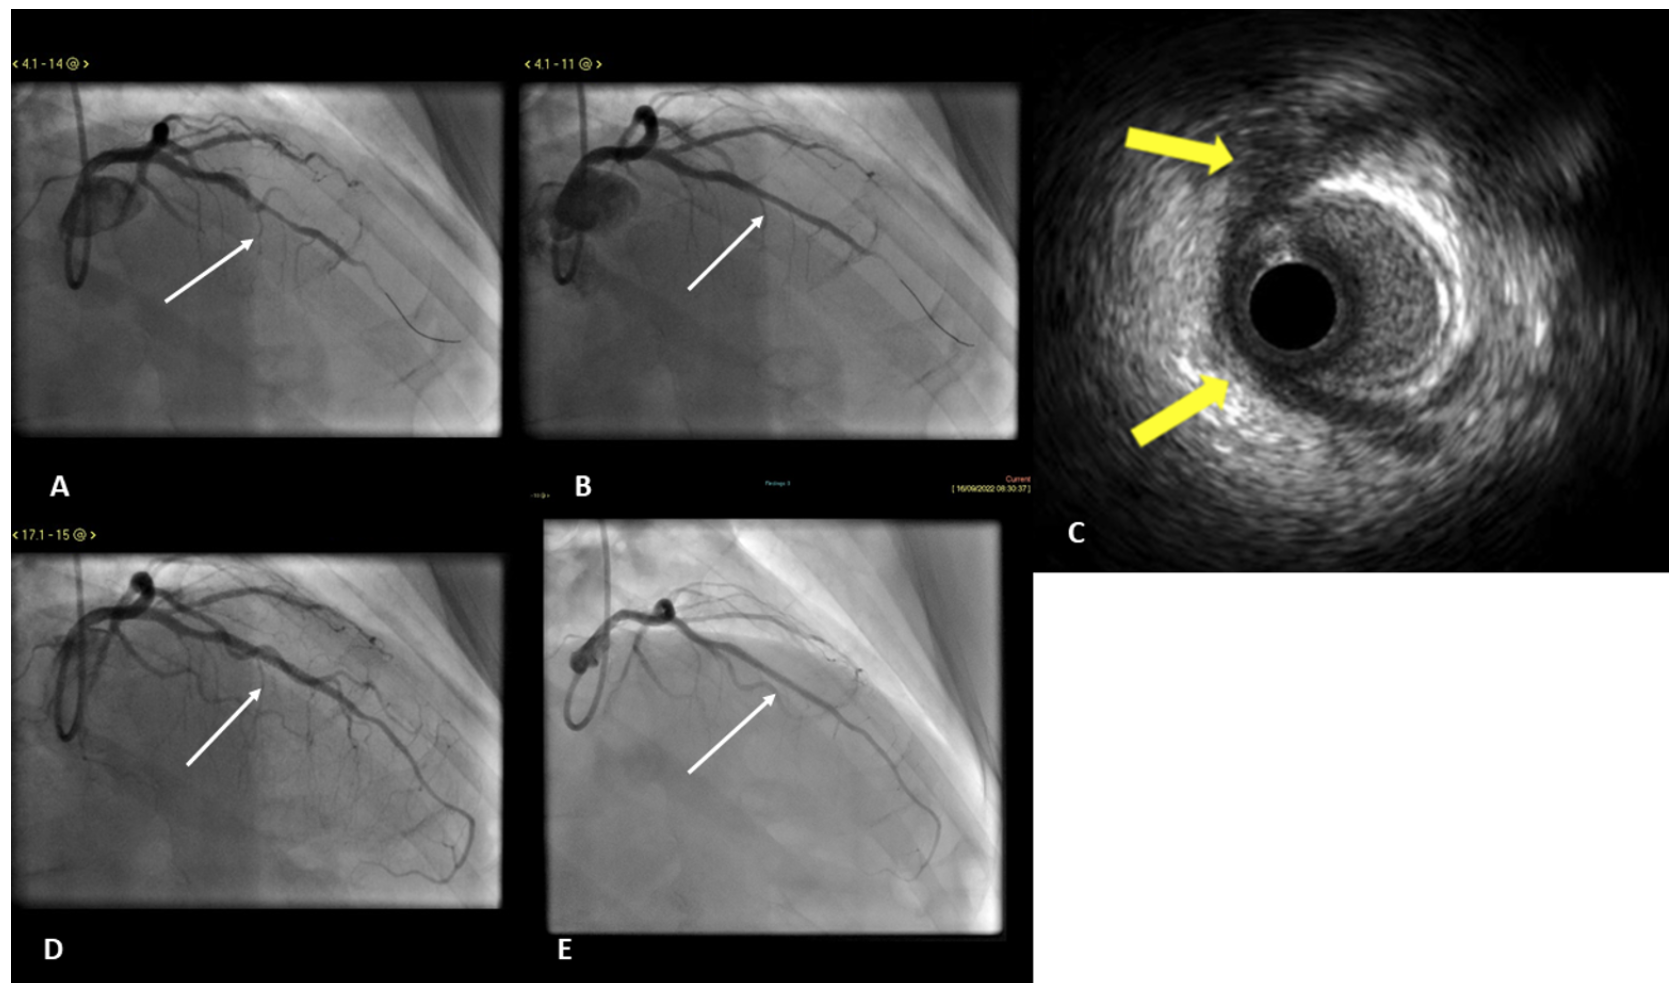

Patient 4. A 54-year-old male patient with exertional angina. Coronary angiogram demonstrated an isolated LAD MB and he was treated with optimal medical therapy for a few months. He continued to experience angina and was brought back for invasive ischemia assessment and consideration for PCI. Physiological functional testing demonstrated that the mid-LAD was hemodynamically significant (RFR of 0.81 and FFR 0.75). IVUS confirmed the presence of MB with characteristic lucent “half-moon” appearance (Figure 4). PCI of the mid-LAD MB was performed with 2 DESs (3.0 x 28 mm and 3.0 x 8 mm) and postdilated with a 3.5-mm NC balloon with excellent angiographic and IVUS results (Figure 4). The RFR after angioplasty rose to 0.92 and FFR to 0.94. At over 20 months of follow-up, the patient had no cardiac symptoms. Repeat coronary angiography at 34 months showed patent stents with no evidence of restenosis.